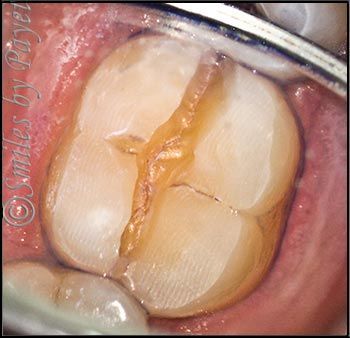

One difficulty with diagnosing cracks in teeth, is that they almost never show up on x-rays. Why, you ask? Good question! It’s because x-rays are traveling perpendicular to the cracks, and the cracks are so narrow, there’s not enough change in the tooth density for the x-rays to show it. To show up on an x-ray, a crack in a tooth would have to be so wide, you could stick a fork in it, and then you’d already know there was a problem. The x-ray shown here is from another patient we recently treated, and while you can’t see anything on the x-ray, want until you see how it looked inside the tooth (on below).

So here’s our patient from yesterday, who’s teeth are a perfect example of what I see all the time (I have more than 3,000 photos of teeth with cracks, taken over the last 12+ years). As you look at the first case, which is getting a crown, you can see how worn down the tooth and old filling are. I’ve highlighted the deep crack with arrows so you can see how far it goes into the tooth – very close to the nerve!